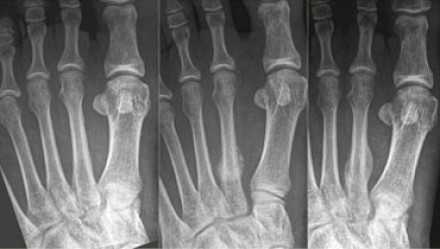

В зависимости от локализации и типа перелома первыми симптомами становятся боль и отсутствие возможности полноценно переносить вес на ногу. При осмотре следует обратить внимание не только на наличие отёка и кровоподтёка определённой локализации, но и на общие анатомические особенности строения стопы (нормальная, кавоварусная, плановальгусная). При оценке амплитуды движений также оценивается степень ротации пальцев стопы, их перекрещивание. В случае застарелых переломов возможны изменения свода стопы в виде коллапса сводов по сравнению с неповреждённой стороной.

Для диагностики обычно достаточно осмотра специалиста и рентгенограмм в прямой и боковой проекции. В случае стресс переломов может возникнуть необходимость в дополнительных методах обследования таких как КТ и МРТ.

Стресс-переломы основания 2-й и 3-й плюсневой кости - «маршевые» переломы. Часто диагноз не удаётся поставить своевременно, так как рентгенологически диагностика на ранних стадиях затруднительна. Переломы часто происходят на фоне резкого увеличения физической нагрузке, изменения характера нагрузки. Боль в стопе сначала тупая и ноющая, постепенно становится всё более острой и локализуется в области повреждения.